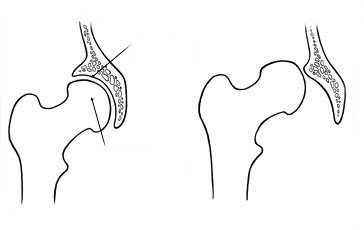

- Bij de geboorte is de heupkop nog niet volledig gevormd. Het is tijdens het eerste levensjaar dat de heupkop zich gaat vormen en de vorm aanneemt van de heupkom waarin hij zich bevindt. Maar bij DDH is deze heupkom te vlak of steil en kan de heupkop eruit glijden.

- Het doel

- is de heup mooi in de heupkom te houden.